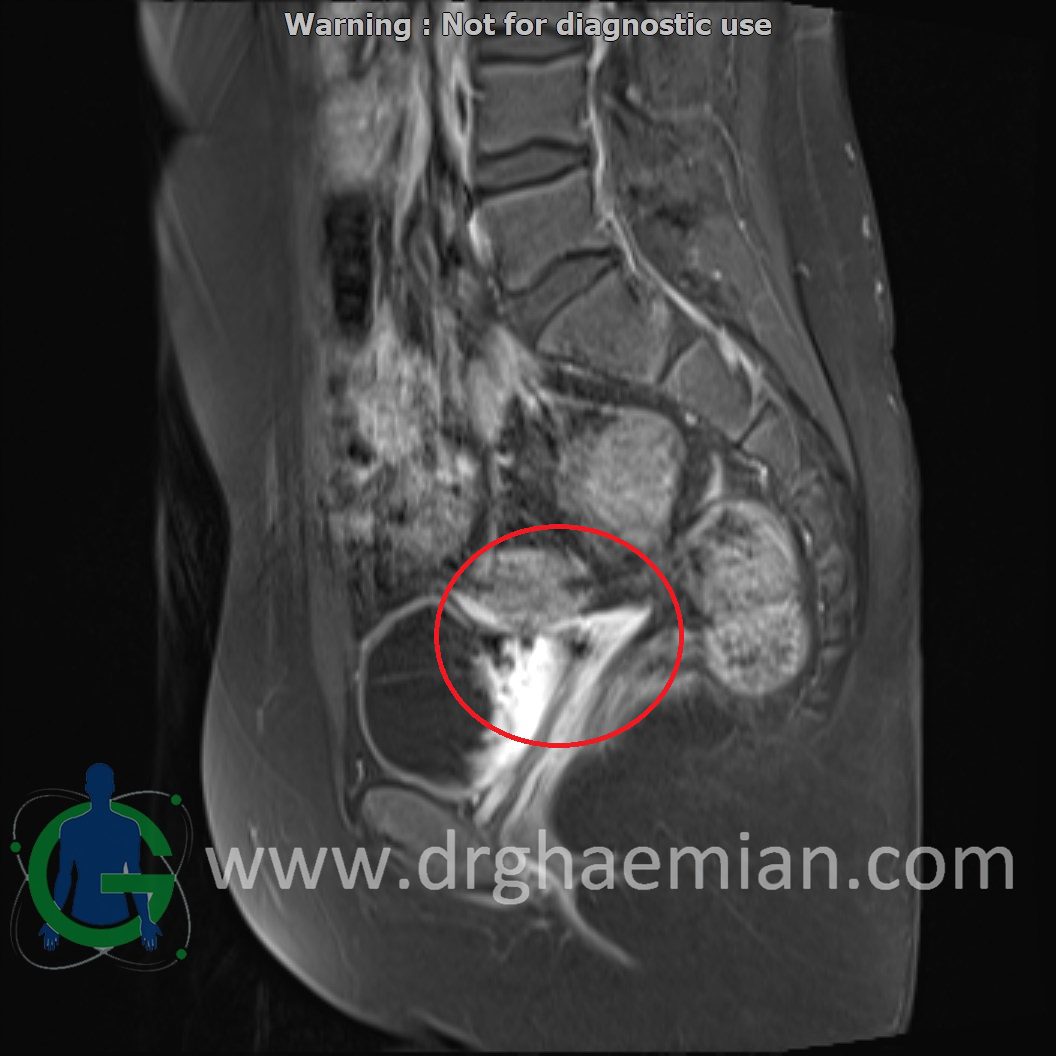

ام آر آی لگن یک روش تصویربرداری است که از طریق دستگاهی با آهنرباهای قوی و امواج رادیویی از ناحیه بین استخوان های ران تصاویری می سازد.در این کیس دیسژنزی غدد جنسی همراه با رحم و واژن هیپوپلاستیک نشان دهننده سندرم سویر ….

Complete gonadal dysgenesis with hypoplastic uterus & vagina suggestive of swyer syndrome is seen.

Clinical crrelation is recommended.